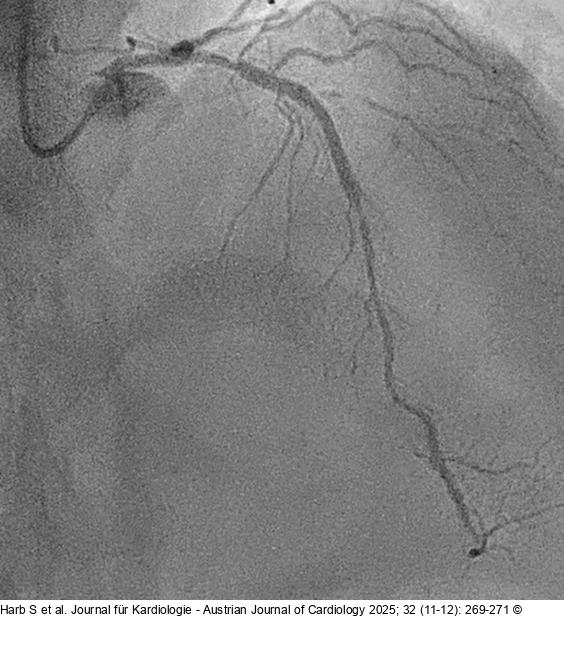

Abbildung 2: Angiography Follow-up angiography showed hazy lesion distal of the stent with significant luminal narrowing, followed by long diffuse lesion |

Follow-up angiography showed hazy lesion distal of the stent with significant luminal narrowing, followed by long diffuse lesion |